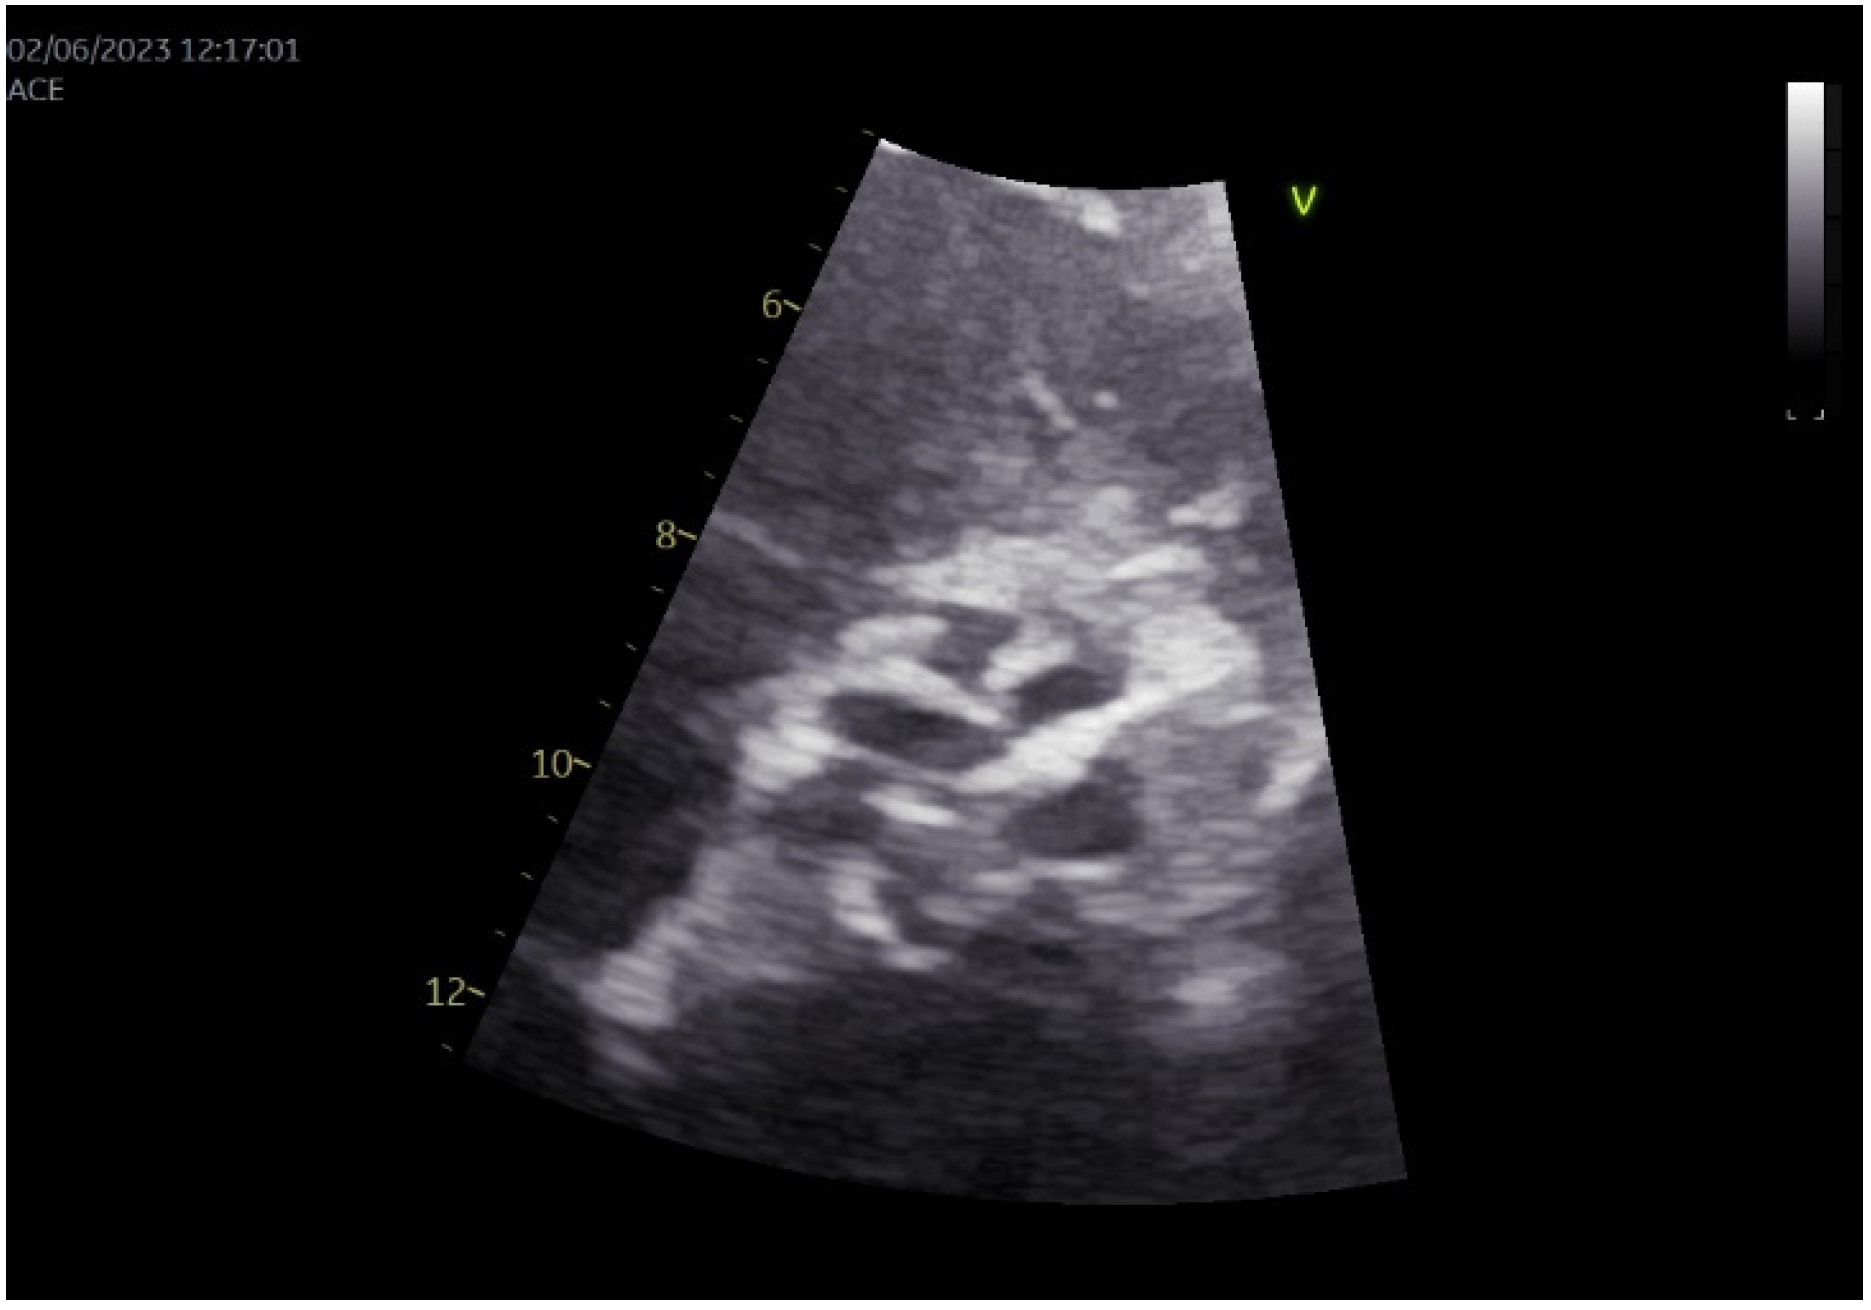

2. Case Presentation

3.8. Our Case